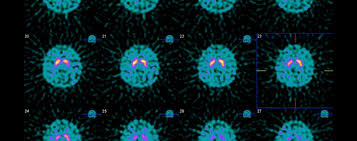

Dopamine Transporter Dat Scan Type 1 Abnormality A Left Side Shows Download Scientific Diagram